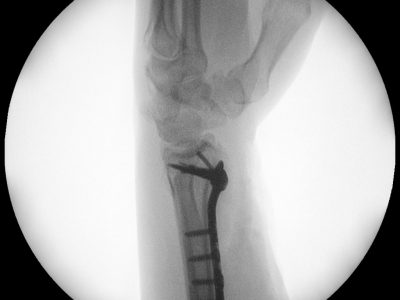

Παρακάτω παρατίθενται ακτινογραφίες καταγμάτων του άνω άκρου που αντιμετωπίζονται με εσωτερική οστεοσύνθεση ή επανορθωτική χειρουργική με αρθροπλαστική.

5. Κατάγματα πηχεοκαρπικής και άκρας χείρας συμπεριλαμβανομένων καταγμάτων σκαφοειδούς και εξαρθρημάτων στα μικρά οστά του καρπού.